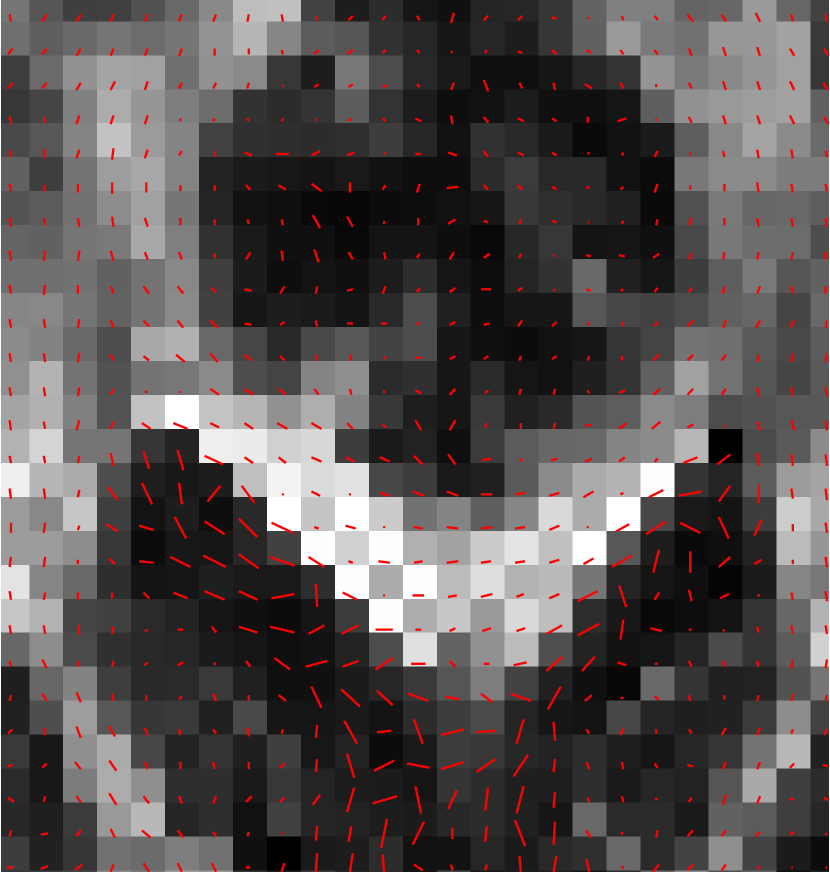

The fact that multiple ’s are needed to recover , leads to very long acquisition times, even with ultra fast sequences like echo planar imaging (EPI). Therefore, DTI is inherently a low-resolution and low-SNR method. In theory, the amplitude DWI images exhibit Rician noise [23]. However, as the histogram of an in vivo measurement in Figure 1 illustrates, this may not be the case for practical data sets from black-box devices. Moreover, the DWI process is prone to eddy-current distortions [50], and due to the slowness of it, it is very sensitive to patient motion [26, 1]. We therefore have to use techniques that remove these artefacts in solving for . We also need to ensure the positivity , as non-positive-definite diffusion tensor are non-physical. One proposed approach for the satisfaction of this constraint is that of log-Euclidean metrics [3]. This approach has several theoretically desirable aspects, but some practical shortcomings [54]. Special Perona-Malik type constructions on Riemannian manifolds can also be used to maintain the structure of the tensor field [14, 51]. Such anisotropic diffusion is however severely ill-posed [weickert1998anisotropic]. Recently manifold-valued discrete-domain total variation models have also been applied to diffusion tensor imaging [6].

Let us try to see, how such intervals might work in practice. For the purpose of the present discussion, assume that the noise is additive and normal-distributed with variance and zero mean—an assumption that does not hold in practice, as we have already seen in Figure 1, but will suffice for the next thought experiments. That is, for the noise . Let the sample mean of be , and pointwise sample variance . The product of the pointwise confidence intervals with confidence is [15, 46]